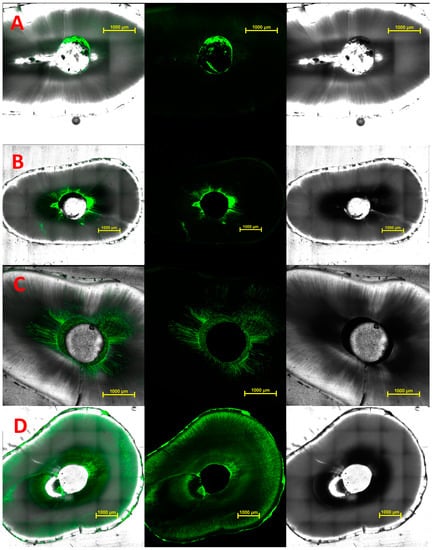

The presence of residual materials on canal walls was identified readily, since remnants showed strong green fluorescence because of the fluorescein label (Figure 5). As shown in Figure 5 panels A and B, remnants of GP could be identified as a shadow on the bright-field images. As shown in Figure 5 panel C, a thin layer of MTAmix™ could be seen coating the walls despite the large volume of the cement which had been removed from the canal.

Figure 5.

Horizontal cross-sections of roots. From left to right, superimposed bright-field image and fluorescence staining, fluorescence staining only and bright-field image only. Remnants of fluorescein-tagged sealer or cement are in green. Image sets are (A) AH-Plus™; (B) Zirmix™; (C) MTAmix™; and (D) Supercal™. Scale bars are 1 mm.

With all products, material that was located within lateral canals or small fins was not removed by the ParaPost™ drill, hence this region was regarded as non-accessible. Removal of 5 mm of Nex MTA™ from the canal was not possible due to the inherent resistance of this material to drilling, and so this group (Group 3) was excluded from further analysis.